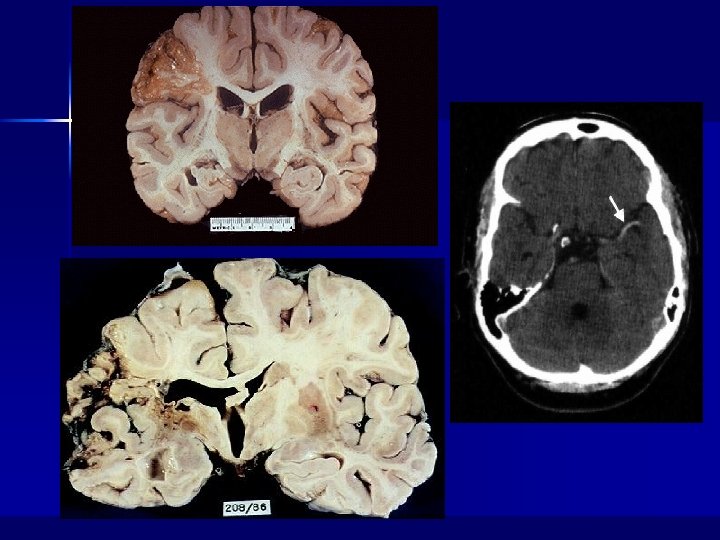

Hemorrhageae in the infarctus area